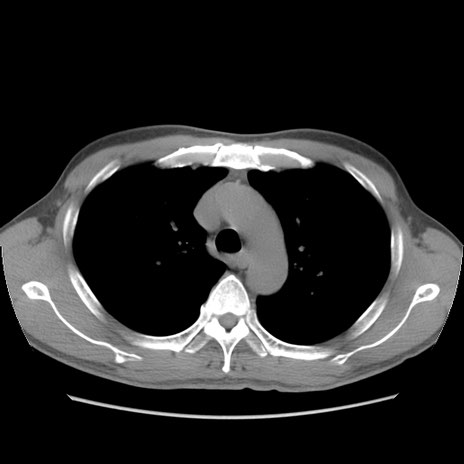

症例56 CT(横断像)

脂肪ウインドウ